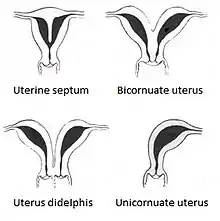

A unicornuate uterus represents a uterine malformation where the uterus is formed from one only of the paired Müllerian ducts while the other Müllerian duct does not develop or only in a rudimentary fashion. The sometimes called hemi-uterus has a single horn linked to the ipsilateral fallopian tube that faces its ovary.[1]

The uterus is normally formed during embryogenesis by the fusion of the two Müllerian ducts. If one of the ducts does not develop, only one Müllerian duct contributes to the uterine development. This uterus may or may not be connected to Müllerian structure on the opposite site if the Müllerian duct on that site undergoes some development. A unicornuate uterus has a single cervix and vagina. Associated defects may affect the renal system, and less common, the skeleton.

The condition is much less common than these other uterine malformations: arcuate uterus, septate uterus, and bicornuate uterus. While the uterus didelphys is estimated to occur in 1/3,000 women,[3] the unicornuate uterus appears to be even more infrequent with an estimated occurrence of about 1/4,000.[2]